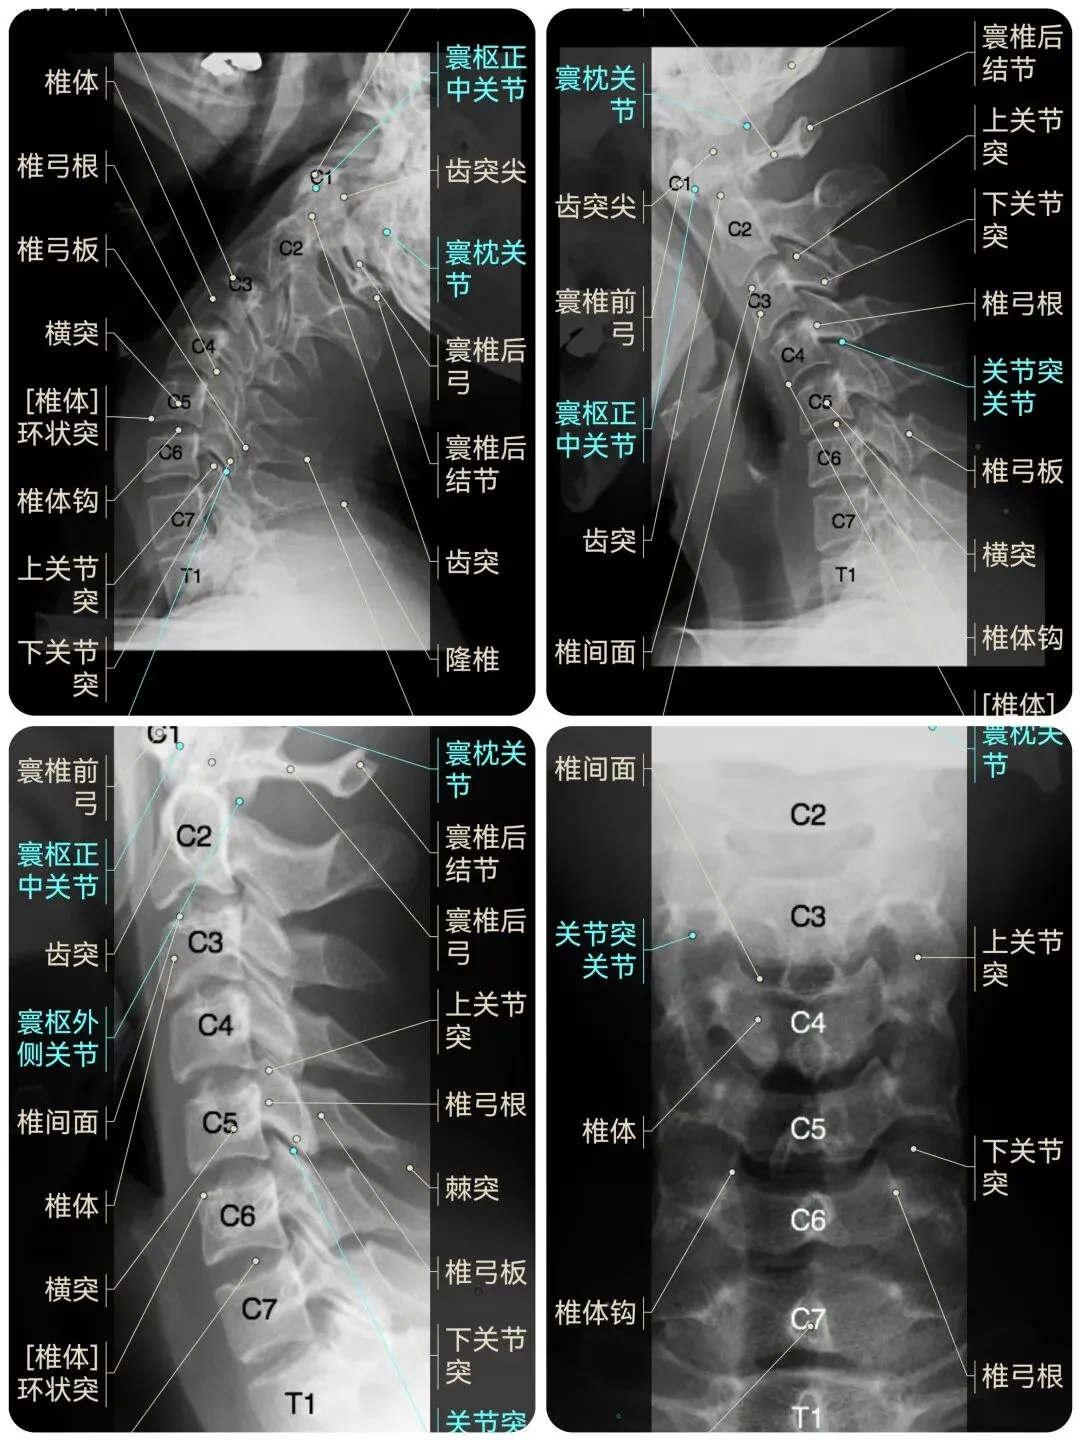

🌈这是国外引进的一款专业影像解剖学习软件。

覆盖了X光、CT、MRI、断层大体解剖、核医学、介入造影、医学插图等多个模块,覆盖全身各个系统的影像解剖(正常解剖结构,无病例),其中的解剖结构高达87万个,结构标注超精细,超高清图像,历时两年研发设计完成✅。